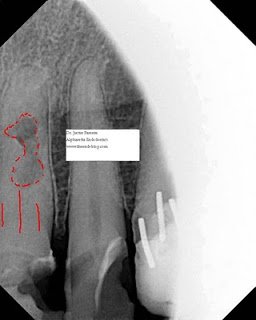

This last case is open to the most controversy. This patient had multiple large composite restorations across the anterior maxillary dentition. He admitted to being far more motivated by financials than esthetics. His previous composite restoration and crown had sheered off unconventionally at an oblique angle to the buccal leaving a substantial cingulum. The fractured portion had been rebonded by his general dentist. This tooth had a history of trauma over 40 years ago and some extensive external resorption is visible overlapping an obliterated pulp chamber and canal. The PDL is definitely in tact and there is no history of symptoms. The option of extraction and implant placement was discussed and encouraged. The alternative treatment plan chosen by the patient is less than ideal and the patient was more than okay with a compromised long-term prognosis. I intentionally described a grim outlook to the patient, as I do with most unconventional treatments, although here I can admit that I am confident in the predictability of the patient’s choice. As you can see from the preop radiographs, conventional root canal therapy is impossible due to the irregular resorptive defect sandwiched between obliterated canal space.

I am still waiting on the general dentist to forward over a restored recall radiograph. Hopefully I will have the image to edit in by the end of the week. You can see the post space that I prepared using a 2 round bur and a gates-glidden with the tip flattened. The post space communicated with the resorptive more coronal than I anticipated, necessitating the use of MTA as a sort of resorptive cap. I feel as long as the area remains aseptic, it is reasonable to assume a successful result.